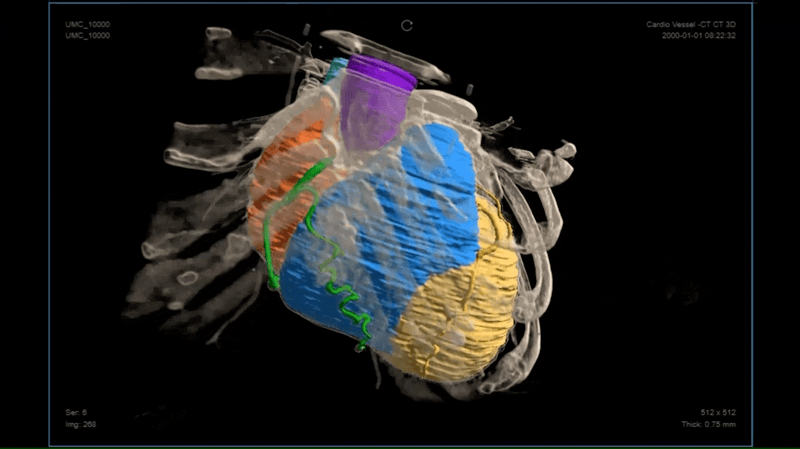

提供面向多场景的医学影像高级可视化呈现

帮助医学院校师生结合真实的医学场景和案例数据,进行虚拟实践和训练,提升技能和专业水平。帮助医生在影像上进行手术模拟和预演,帮助医生向患者解释病情和治疗方案,帮助患者更好地理解自己的疾病,从而更积极地参与治疗过程。